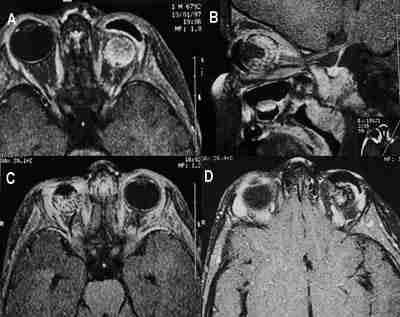

53-04.jpg (6514 bytes)

Figuras 4a, b y c. Glioma del nervio óptico. Secuencia axial potenciada en T1 tras la administración de Gadolínio (a, b) que muestra el tumor del nervio óptico derecho que no llega al quiasma. Una reconstrucción biplanar (c) logra delimitar mejor la extensión tumoral así como su componente quístico.

53-05.jpg (13291 bytes)

Figuras 5a y b. Rabdomiosarcoma orbitario izquierdo. Secuencia potenciada en T1 con gadolínio y saturación grasa (a) y potenciada en T2 (b). El tumor impronta el globo ocular y el cono muscular.

La RM muestra una masa de intensidad de señal similar al músculo o al cerebro en T1, hiperintensa en T2. La intensidad de señal puede variar si el tumor presenta áreas de hemorragia focal. El realce con contraste paramagnético es moderado-marcado.

La RM demuestra la extensión del tumor a senos paranasales (seno etmoidal) así como al compartimento intracraneal a través de la fisura orbitaria inferior.

53-06.jpg (13316 bytes)

Figuras 6a y b. Granuloma eosinófilo que destruye el techo orbitario izquierdo e invade el parénquima cerebral. Secuencias de RM potenciadas en T1 con Gadolínio coronal (a) y sagital (b).

53-07.jpg (12729 bytes)

Figuras 7a, b, c y d. Neurinoma extraconal. Secuencia sagital T1 (a) y axial DP que muestra la lesión de localización extraconal. Las reconstrucciones coronales en ventana ósea (c) y parenquimatosa (d) de TC helicoidal permiten ver la lesión pue produce remodelación ósea, hallazgo típico de las lesiones de lento crecimiento.